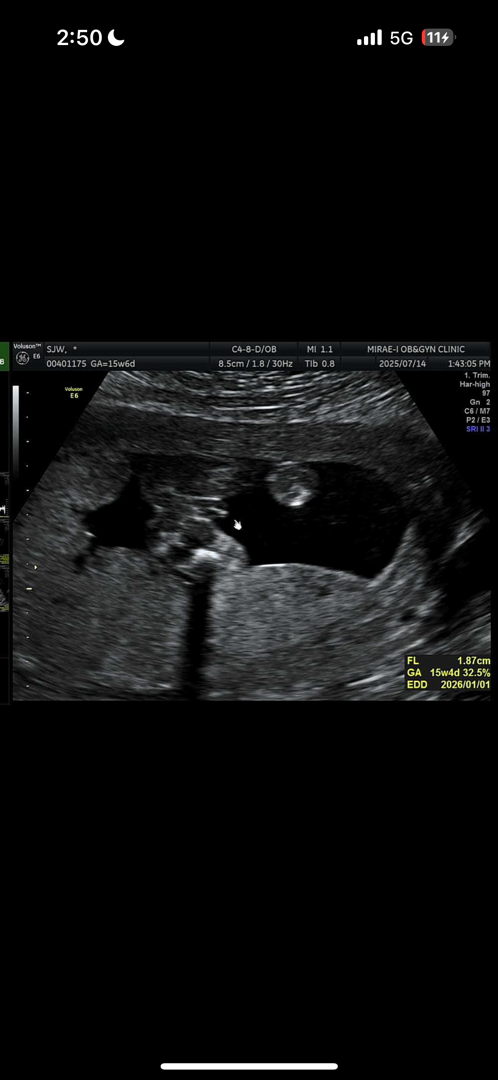

16주차 초음파 성별

지난주에도 다른 외래때문에 초음파 볼 일이 있어서 봤는데 딸이라고 했었거든요 ㅠㅠ 근데 정기검진 어제 다녀왔는데 또 아들같다고 ㅠㅠㅠㅠㅠㅠㅠㅠ 한번 봐주세요

딸같아요 생식기쪽이 ll 모양으로 생겨서용

딸에서 아들은 흔해요 저도그랬구여ㅋㅋ안보여주다가 딸이라하셨는데 니프티검사하니 아들 그뒤로 일주일뒤 꼬추가뿅ㅋ아들같아유~